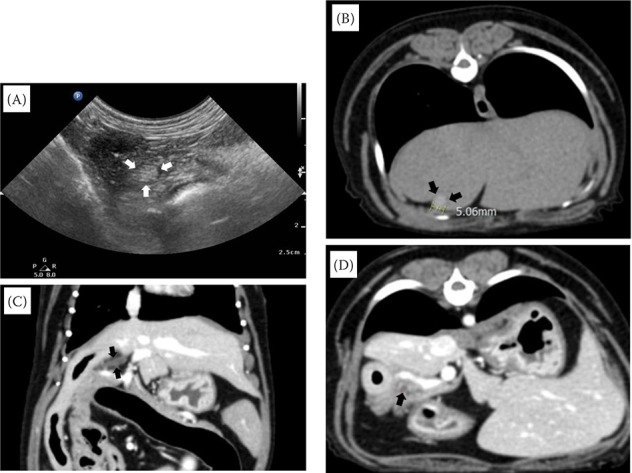

In a recent case study, researchers have shed light on an uncommon but significant condition in veterinary medicine - gallbladder atrophy (GBA) in dogs, particularly associated with pancreatitis. This condition, characterized by a reduction in gallbladder size and volume, is known in human medicine to often occur alongside gallbladder and pancreas pathologies. However, its documentation in canine patients is relatively sparse.